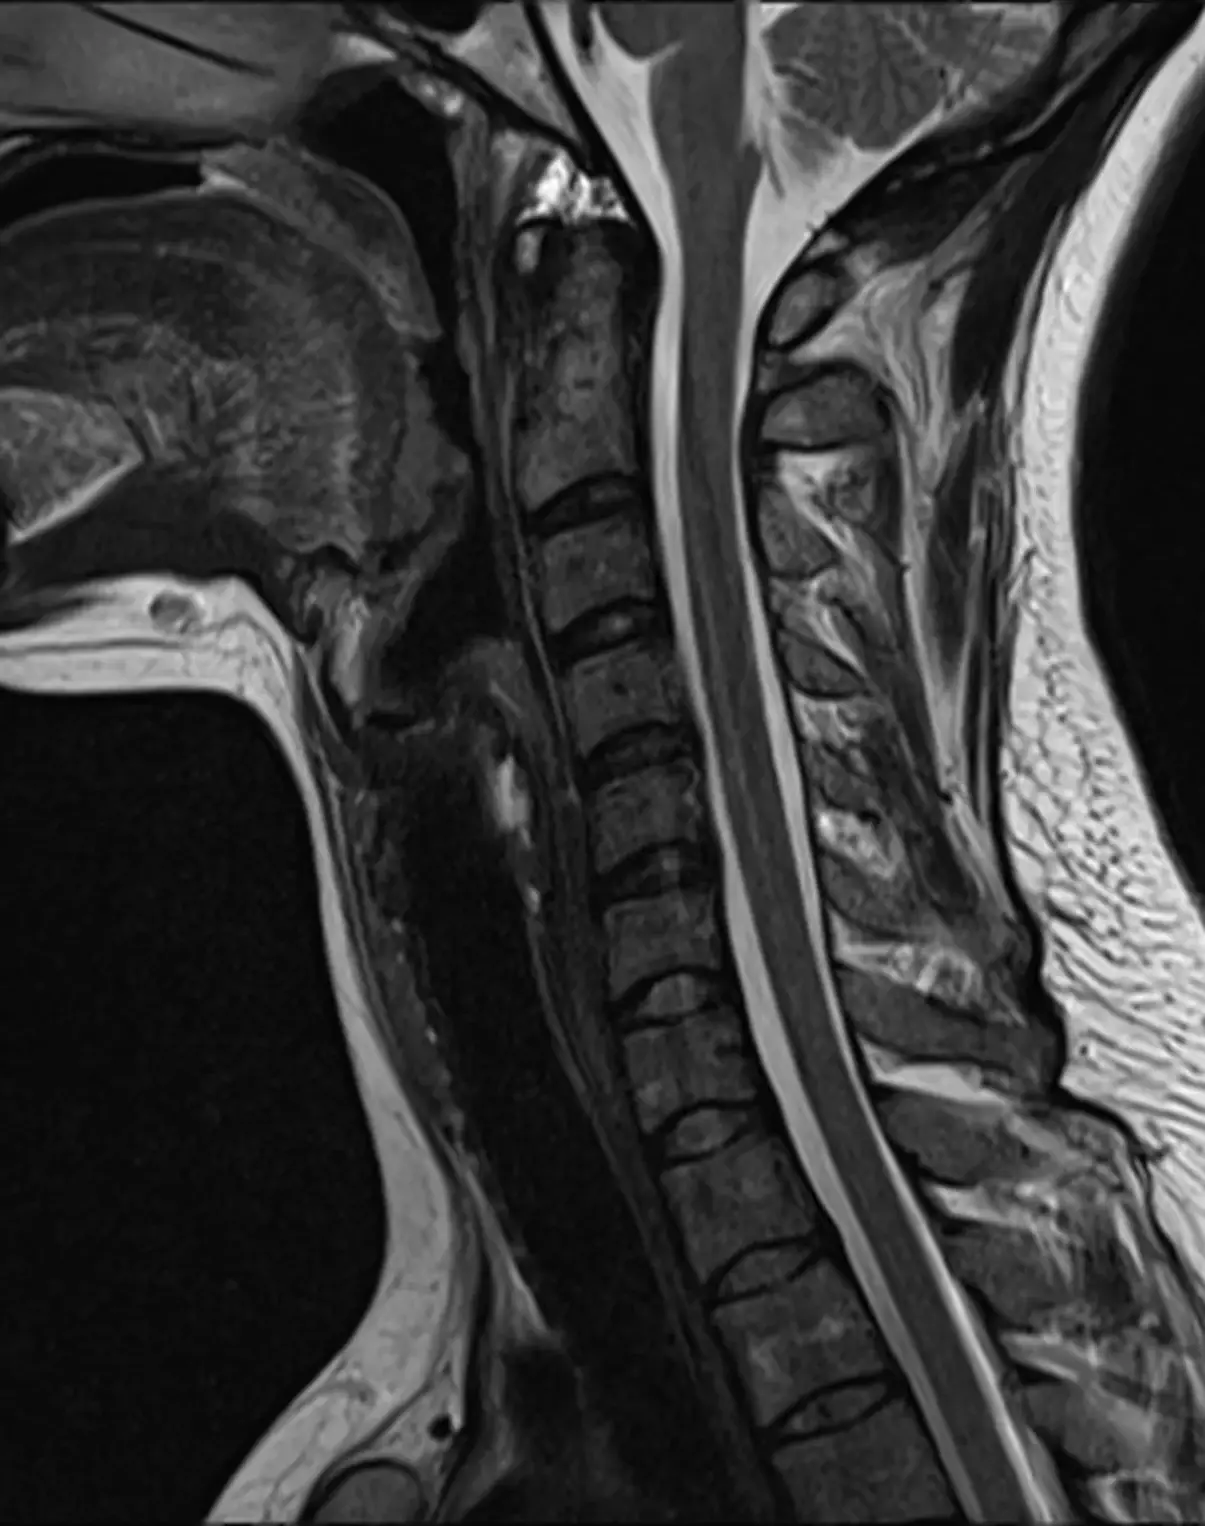

МРТ шейного отдела позвоночника

Визуализация позвонков, межпозвонковых дисков, атланто-окципитального сочленения, зубовидного отростка, хода позвоночных артерий, спинного мозга, спинномозговых корешков, окружающих мягких тканей.